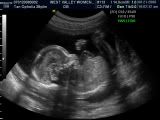

Here's little beanie... Isn't he cute and round?

We think he has daddy's nose! Cause its all sharp and pointy... Mummy's really flat! Hehe...